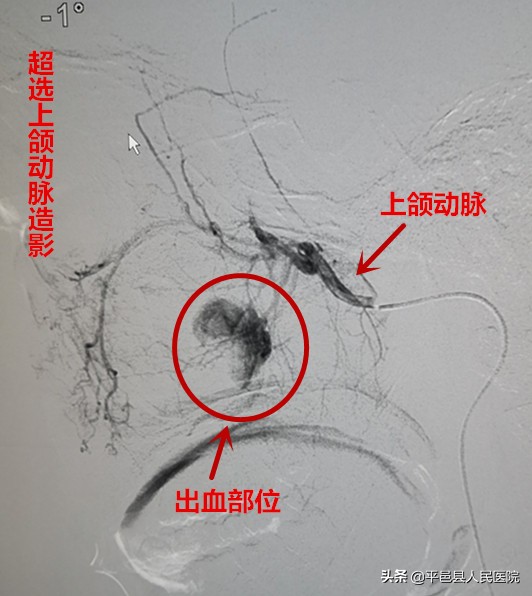

放射介入科行左侧颈外动脉造影发现患者出血原因为外伤后致左侧上牙槽后动脉破裂所致,紧急栓塞该血管,术中血管造影显示出血停止。术后患者未再出现鼻出血,康复出院。